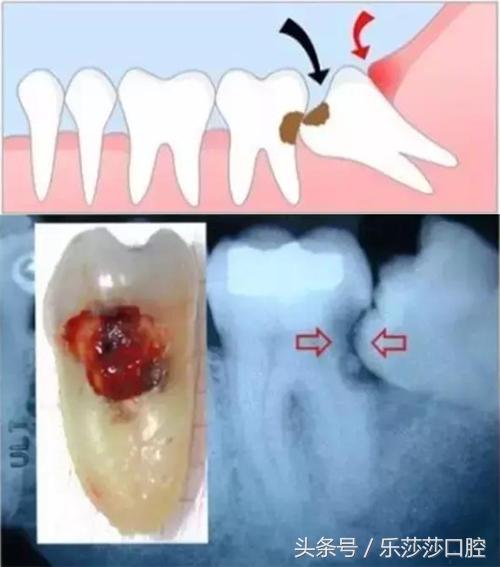

五、阻生智齿:因「颌骨」没有足够的空间,导致「智齿」被阻生在颌骨内并向其他方向生长,最后与邻牙成死角发生「龋坏」。